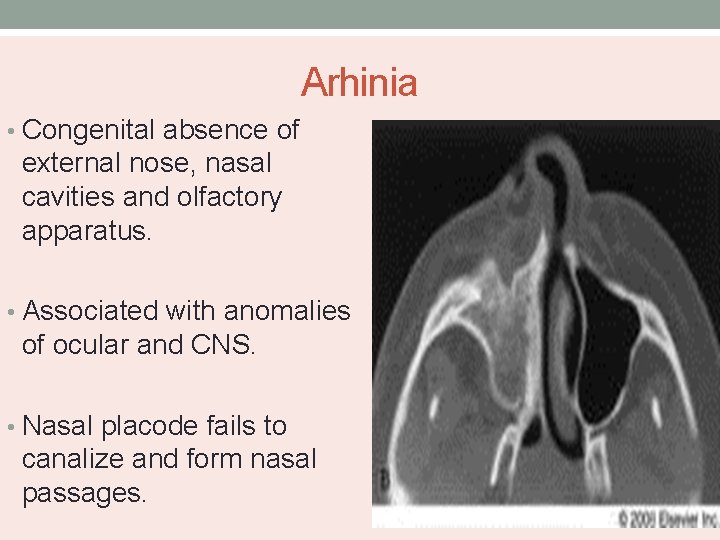

Arhinia • Congenital absence of external nose, nasal cavities and olfactory apparatus. • Associated with anomalies of ocular and CNS. • Nasal placode fails to canalize and form nasal passages.